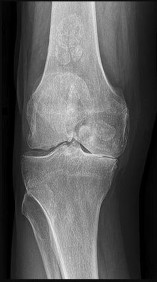

Figures 6a through 6d are the radiographs and T1-weighted sagittal and fat-saturated axial MR images of an otherwise healthy 56-year-old man who has anterior knee pain and intermittent swelling after sustaining a noncontact twisting injury. Low-power and high-power hematoxylin and eosin stained histologic specimens are shown in Figures 6e and 6f. Based on the history, radiographs, CT scan, MR imaging, and histologic findings, what is the most likely diagnosis?

The lesion in the posterior intercondylar knee notch is a benign synovial hemangioma. Intralesional calcifications, classically associated with hemangiomas, are frequently not identified on plain radiographs. The MR imaging reveals a hypervascular lesion with multiple filling defects, with hyperintensity on T2-weighted images and low-to-intermediate signal intensity on T1-weighted images. Histologically, vascular lakes within fine capillaries with a synovium on the surface of the lesion are characteristic of this condition. Many patients with synovial hemangioma have pain, swelling, stiffness, or mechanical symptoms. The correlation of symptoms with the hemangioma for this patient is unclear because there was recent trauma and a concurrent meniscus tear. Simultaneous treatment of both potential sources of pain is typically recommended. As with PVNS, the disease can be localized or diffuse. Surgical excision, either open or arthroscopic, is the recommended treatment. PVNS is the most common intra-articular tumor, but hypointensity in either the diffuse or localized type is characteristic in both T1- and T2-weighted images. Synovial sarcoma, although often found close to a joint, is not characteristically found within a joint.